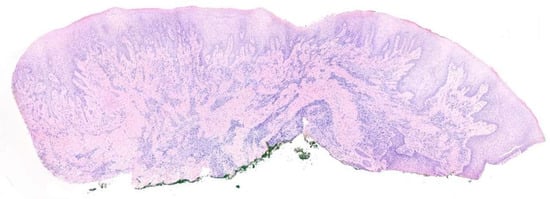

2.2. Histopathological Examination